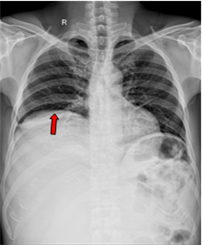

Ca lâm sàng: Điều trị đích bệnh nhân ung thư phổi không tế bào nhỏ giai đoạn muộn di căn nhiều cơ quan, tại Trung tâm Y học hạt nhân và Ung bướu – Bệnh viện Bạch Mai

Ung thư phổi là nguyên nhân hàng đầu gây tử vong do ung thư trên toàn thế giới. Trong đó, ung thư phổi không tế bào nhỏ (NSCLC) là thể thường gặp nhất, chiếm khoảng 85% các trường hợp [1]. Phần lớn bệnh nhân được chẩn đoán ở giai đoạn tiến...